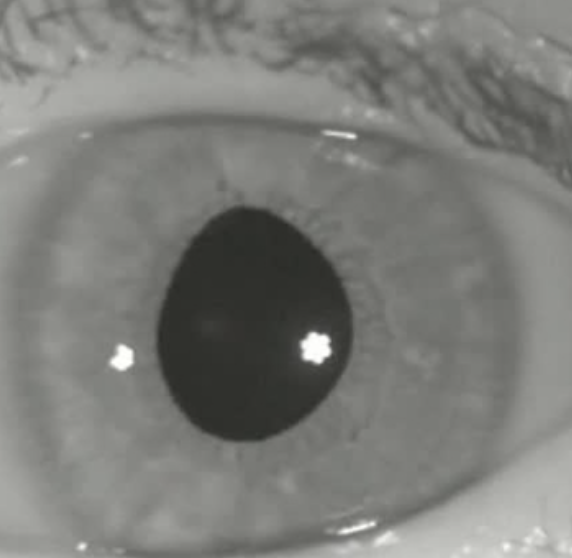

Irregularly shaped irises

4 Abnormal Findings for 11. Inspect iris and pupil

Irregularly Shaped Iris

4 Abnormal Findings for 11. Inspect iris and pupil

Causes a shallow anterior chamber, which may increase the risk for narrow-angle (closed-angle) glaucoma